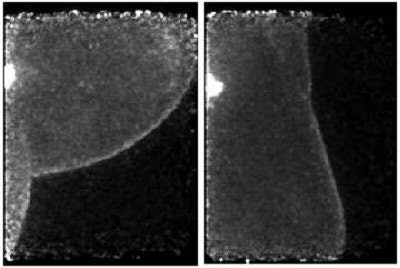

![]() |

| With PEM, a lesion can be seen in the mammary fold (left) and in low axillary lymph node (right). |